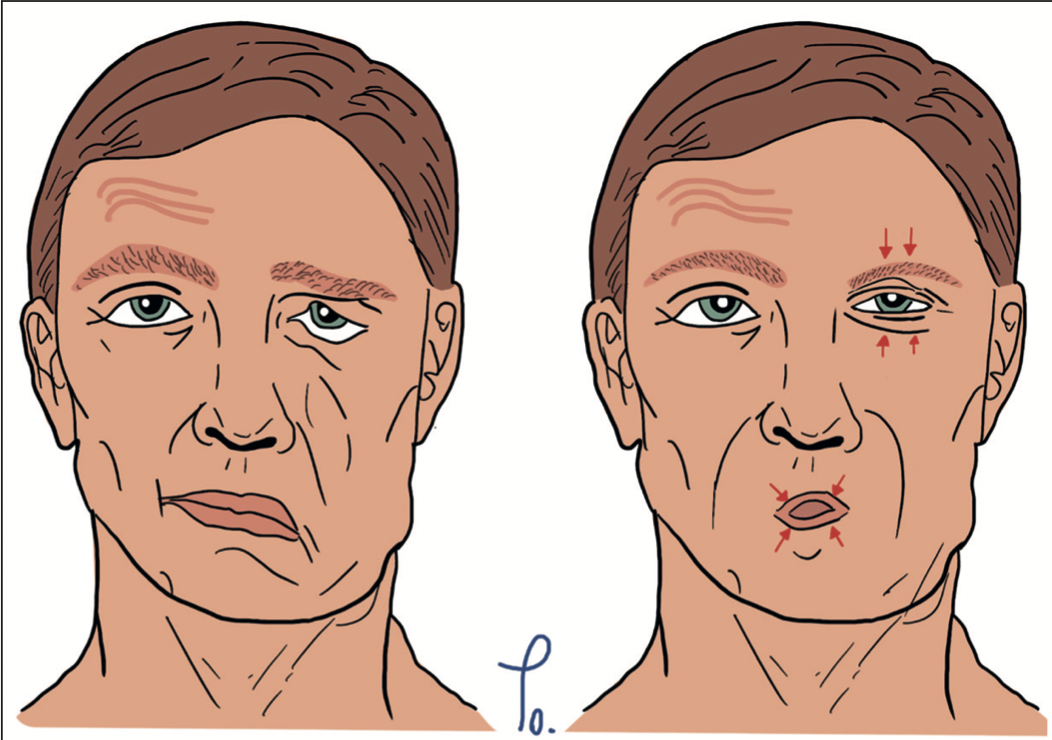

Gunther Mangelsdorff, Gregorio Maturana Cortés, Miguel Obaid

|

|

|